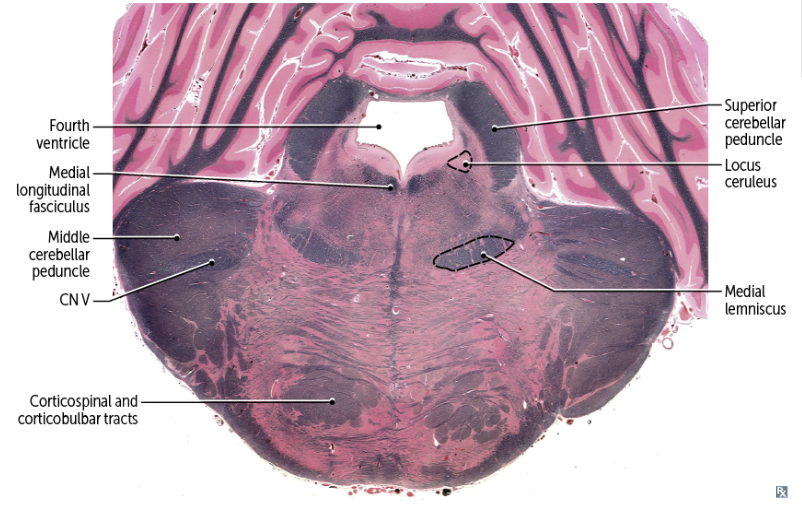

16

Q

recognizable features of the PONS in cross-section

A

-anterior/ventral: bulging fibers (little belly)

-posterior/dorsal: 4th ventricle